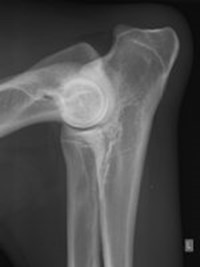

Queste malattie ereditarie colpiscono molte razze canine durante la crescita, causando dolore e riducendo la qualità della vita. La displasia dell’anca è una malformazione in cui la testa del femore non si adatta perfettamente alla cavità del bacino, mentre la displasia del gomito comporta una crescita disarmonica delle ossa che compongono l’articolazione.

Le displasie possono essere diagnosticate precocemente con esami radiografici eseguiti dal quinto/sesto mese di vita. Questi esami, effettuati in sedazione, includono proiezioni specifiche per anca e gomito e sono essenziali per intervenire tempestivamente.

Nello specifico lo studio dell’anca prevede ben 4 proiezioni (antero posteriore standard, in distrazione, a rana e dar).

Lo studio del gomito prevede due proiezioni (latero /laterale e antero posteriore).